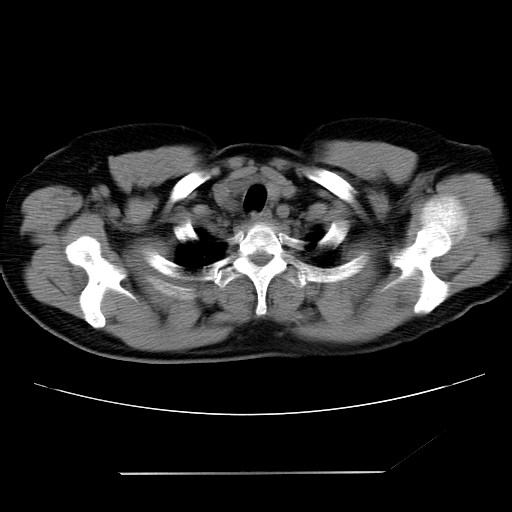

女性,62岁,长期咳嗽,既往从事工作有粉尘接触,有高血压病史,110/150mmhg,近日咳嗽加重,脸面浮肿,请大家帮看下,

1、尘肺;2、慢性支气管炎合并肺部感染;3、心影增大(左房、左室大),考虑高血压性心脏病。

慢支并肺部炎症;右肺结核球?主肺动脉、右肺动脉影不宽,右心室不大,不支持肺心病;无心包积液。